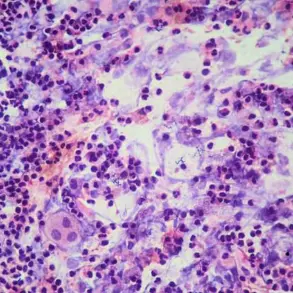

SYNGAP1-related disorders (SRDs) represent a complex and often misunderstood category of genetic conditions that can lead to a range of neurological challenges, including autism spectrum disorder (ASD) and epilepsy.

While these disorders are not the sole cause of all autism or epilepsy cases, they are estimated to account for one to two percent of all intellectual disability cases, including ASD and epilepsy.

The disorders are considered a spectrum because the faulty genes responsible for SRDs often manifest differently in the brain, affecting severity and symptoms in unpredictable ways.

Epilepsy, a common symptom in patients with SRDs, affects more than 80 percent of those diagnosed with SYNGAP1-related brain disorders.

With approximately 470,000 children in the U.S. living with epilepsy, the condition is a major public health concern.

Experts emphasize that epilepsy is influenced by both genetic and lifestyle factors, complicating efforts to develop universally effective treatments.